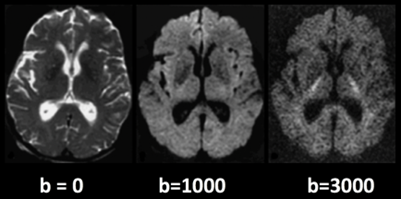

DTI fiber tractography of human brain

DTI fiber tractography is a powerful tool for investigating the human brain's structural connectivity. It enables us to explore the complex network of fiber pathways that connect different regions of the brain and play a crucial role in its function. In this work, I used DWI(Diffusion-Weighted Imaging) data processing software (such as DiffusionToolkit, and Trackvis ) to construct fiber tracks of the human brain based on MRI(Magnetic Resonance Imaging) data and investigated the brain anatomical structure of a human subject using DTI(Diffusion tensor imaging) fiber tractography. The two software I used was Diffusion Toolkit and Trackvis. Diffusion Toolkit did the preparation work for Trackvis, including data reconstruction and fiber tracking on diffusion-weighted MR(Magnetic Resonance) images. Trackvis was utilized for the tractogram visualization and further analyses of the white matter tracts generated by using DTI fiber tractography. In this work, I successfully used Diffusion Toolkit and Trackvis to construct fiber tracks of the human brain, and the results were correct when compared to the standard brain. Besides, I summarized the principle of DTI and the advantages and disadvantages of the technology.